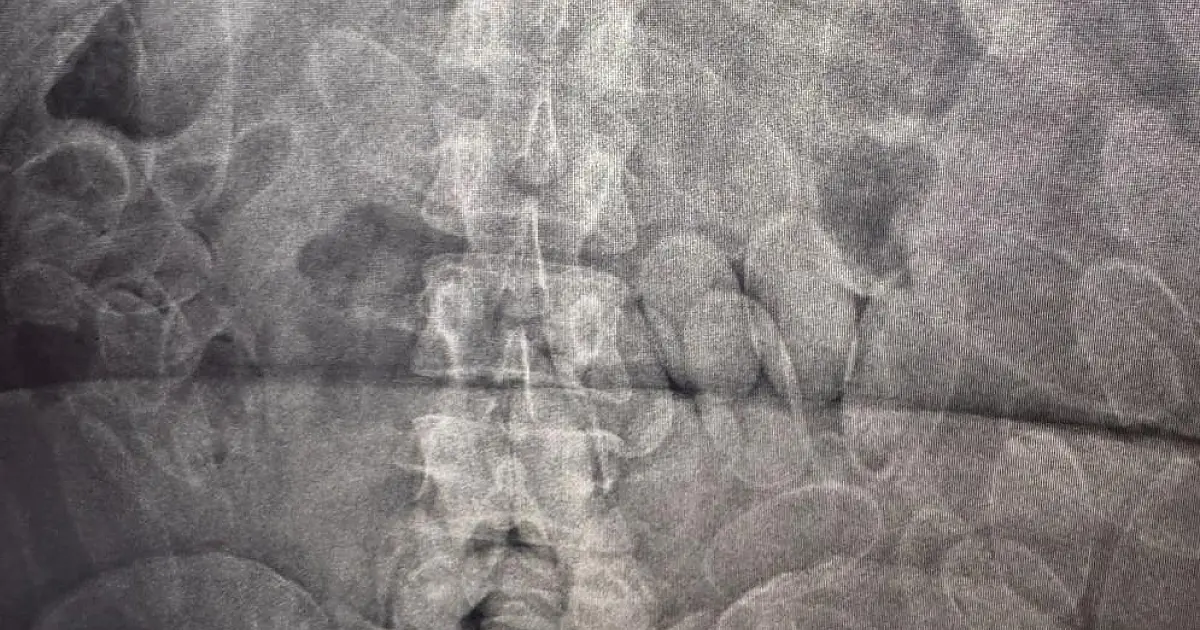

Exame detecta cápsulas de cocaína ingeridas por três bolivianos Cada um dos autores levava cerca de 100 cápsulas dentro do próprio corpo. (Foto: Divulgação/RFB)

Após entrevista, foi identificado indícios de que os três poderiam ter engolido cápsulas de cocaína. Imediatamente as equipes conduziram os suspeitos para a Santa Casa de Corumbá, onde exames confirmaram a suspeita. Cada um dos indivíduos levava cerca de 100 cápsulas de cocaína dentro do próprio corpo, o equivalente a aproximadamente 3,5 kg.